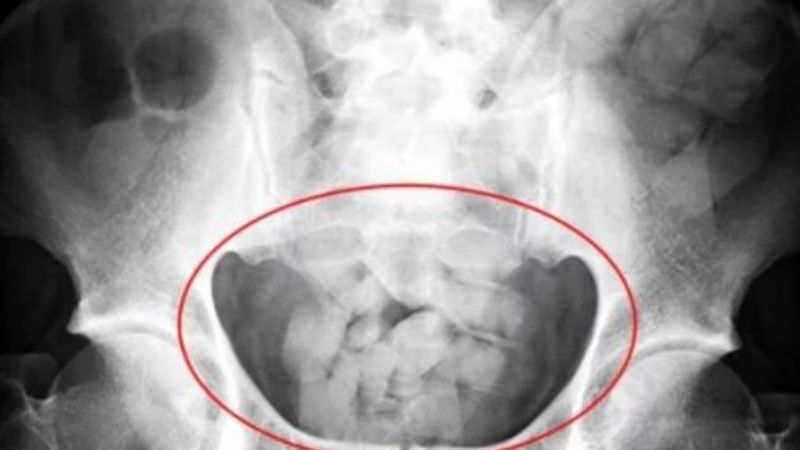

Dos ciudadanos de nacionalidad boliviana fueron detenidos ayer en la Terminal de Omnibus, acusados de transportar drogas en el interior de su cuerpo.

Tras ser llevados al Hospital, uno de ellos arrojó casi un kilo de cocaína que había ingerido y tenía en su estómago; mientras que el otro expulsó medio kilo. Este último se encuentra en grave estado de salud.